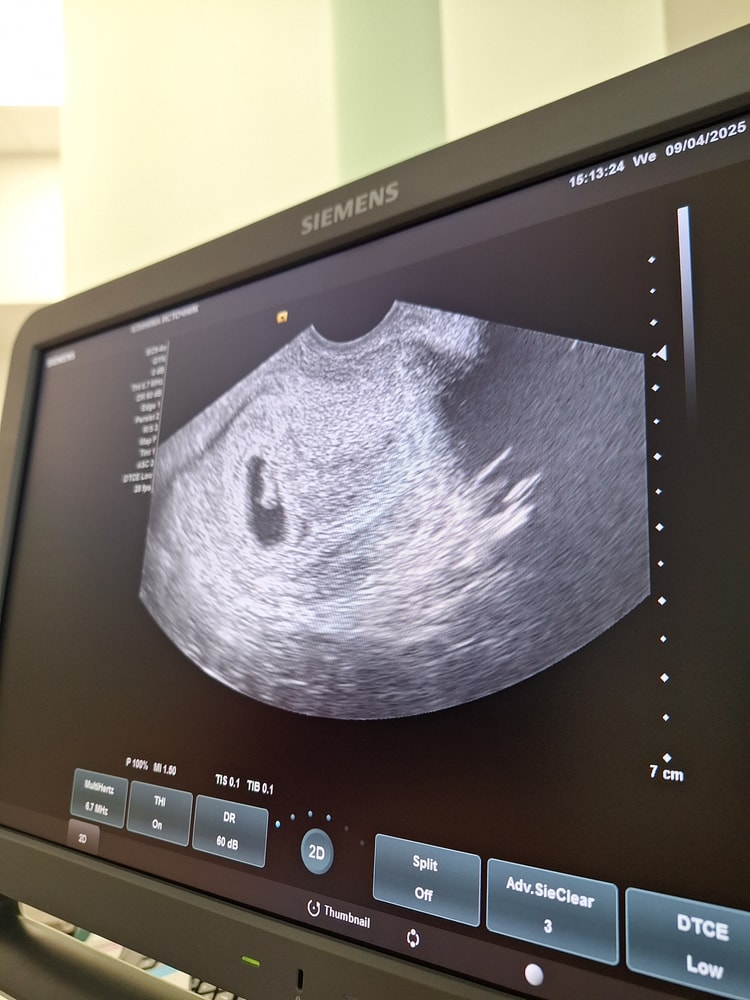

Беременность 6 недель